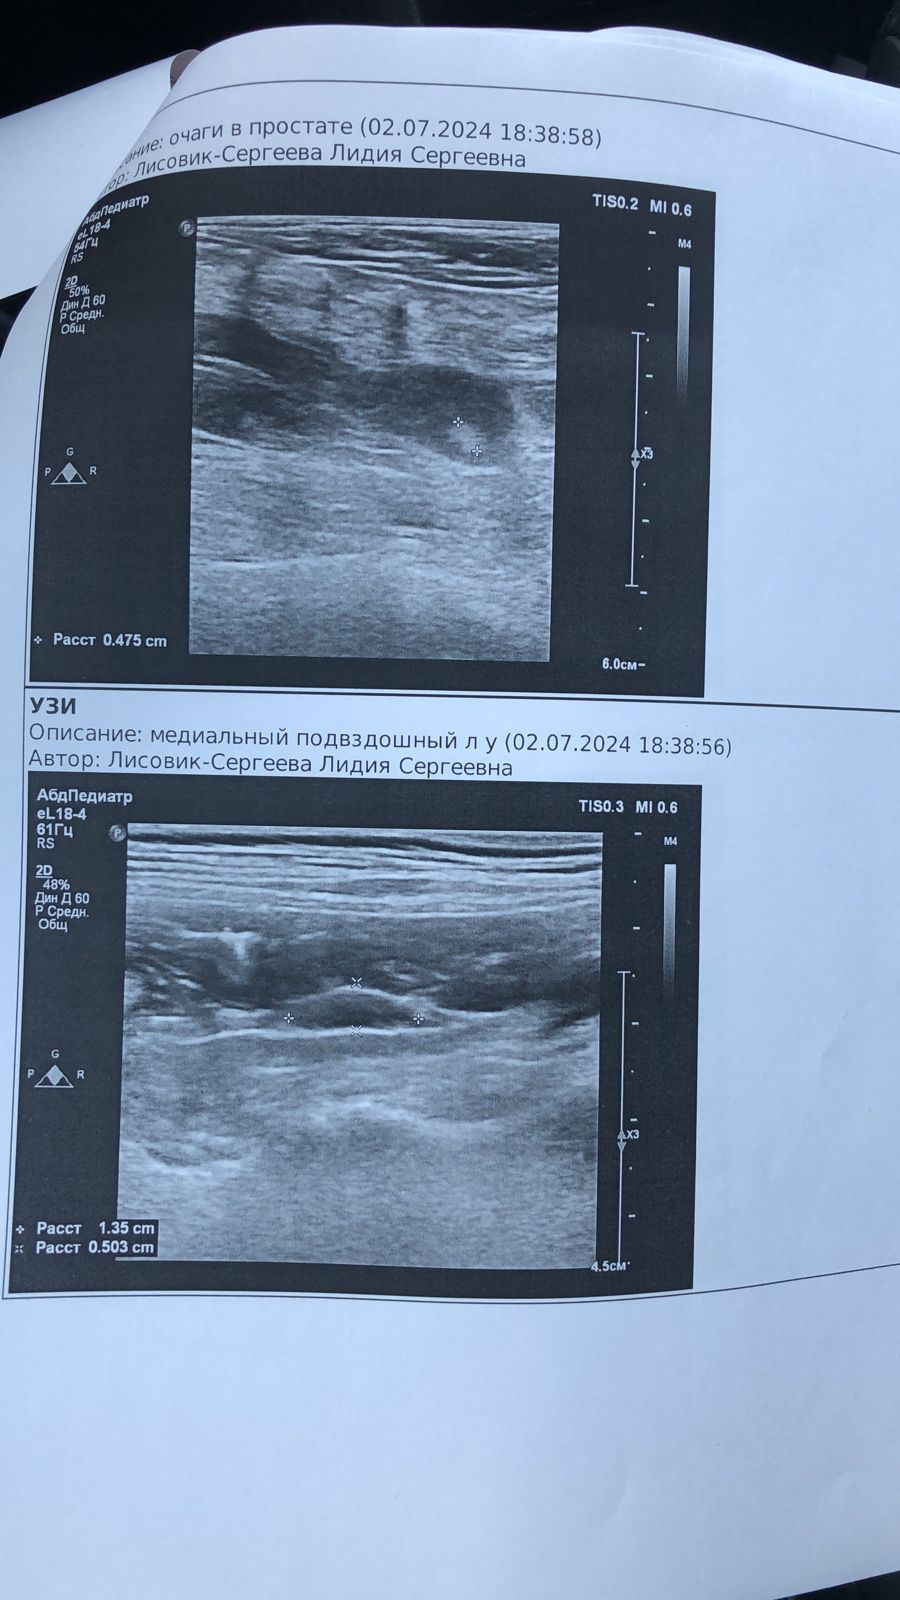

Поездка к онкологу и на УЗИ

Вложения